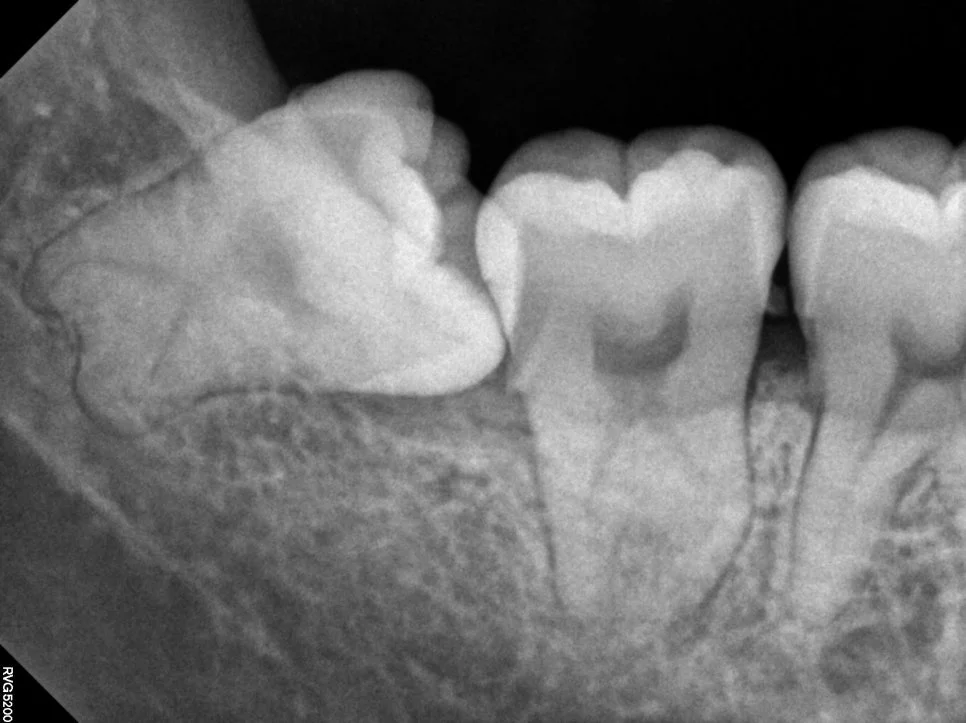

우측 매복 사랑니 진단

매복 사랑니 우측 치근단 X-ray 수평 매복

우측 치근단 X-ray (수평 매복)

제2대구치를 위협하는 우측 하악 매복 사랑니입니다. 잇몸 아래에 완전히 매복되어 있는 상태를 확인할 수 있습니다.